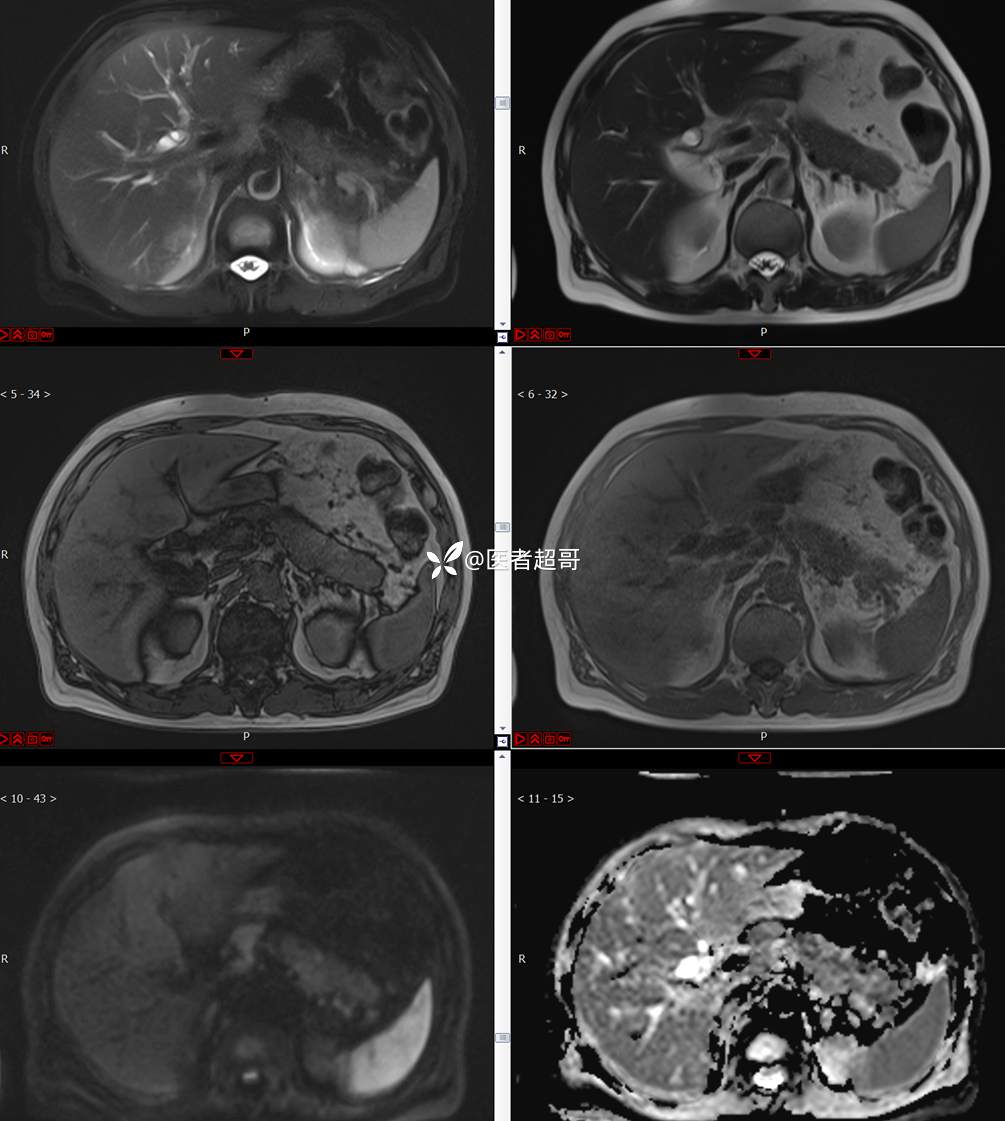

【影诊笔记772】腹痛就诊,发现肾脏病变,CT、MRI齐全,请高诊!

男,63岁 0200825 01

主 诉:间断腹痛15天

现病史:患者15天前无明显原因及诱因出现腹部疼痛不适,呈间断性钝痛,右下腹为著,无尿频、尿急、尿不尽,无发热、寒战,无腹胀。于市中心卫生院住院治疗,超声示:胰头低回声包块,胆系扩张,左肾囊肿,胆囊壁毛糙,胆囊内胆汁淤积。患者为求进一步诊治,遂以“肾盂肿瘤”收入院,患者自发病以来,神志清,精神可,饮食睡眠可,大便无明显异常,近期体重无明显增减。

既往史:既往体健